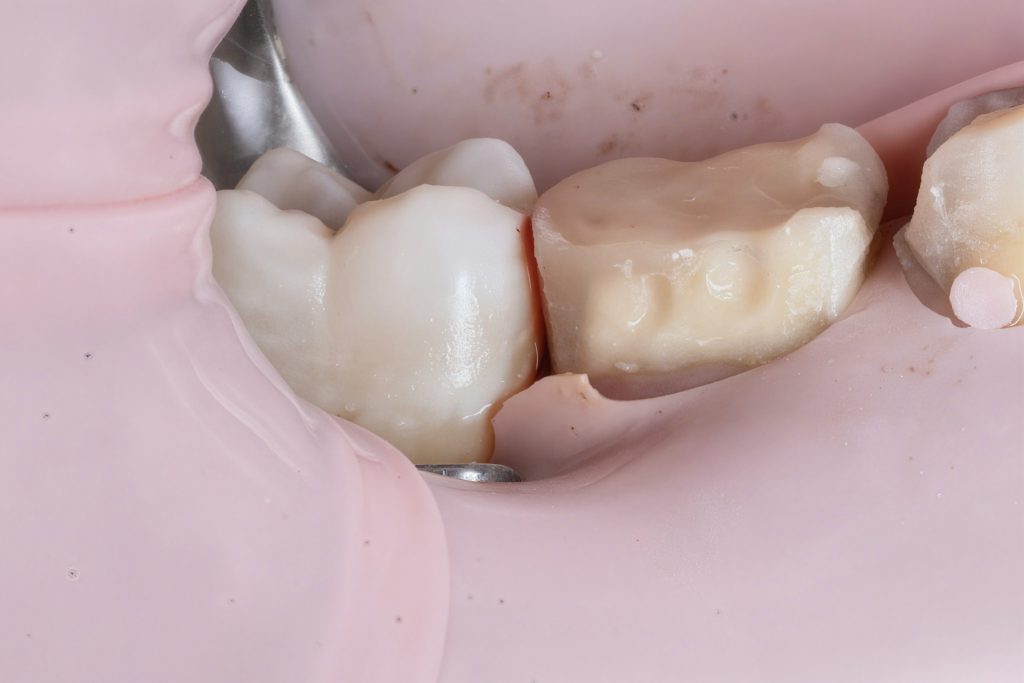

Cervical margin elevated using GC EverX Flow with the matrix-within-matrix technique to re-establish a supragingival margin (Fig 6). Short fibers within the flowable composite acted as an internal stress-absorbing scaffold.

- Fig 6: DME performed with GC EverX Flow.